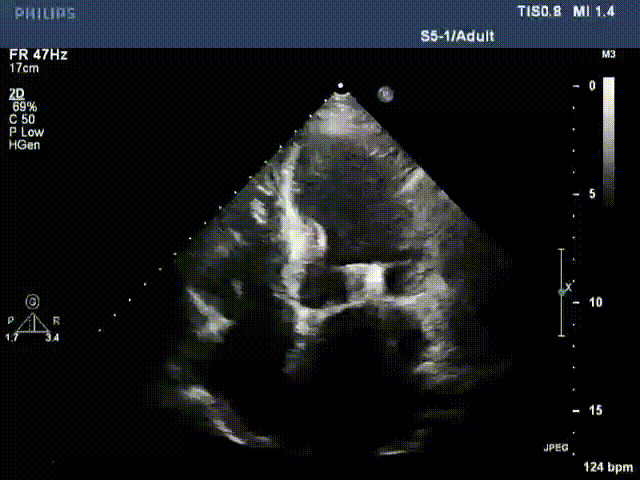

接受治療的是一例器質(zhì)性重度二尖瓣反流(DMR)患者,主訴“反復(fù)活動后胸悶,氣促3年余”。術(shù)前超聲顯示,雙房增大,二尖瓣脫垂伴重度反流,輕度三尖瓣反流,輕度肺高壓,升主動脈增寬。手術(shù)經(jīng)股靜脈-房間隔入路,采用全身麻醉插管,在TEE和DSA引導(dǎo)下完成房間隔穿刺。置入JensClip瓣膜夾系統(tǒng)后,在左房調(diào)整瓣膜夾的位置和軸向,后進入左室,在TEE引導(dǎo)下捕捉二尖瓣前后瓣葉,并關(guān)閉瓣膜夾。經(jīng)TEE反復(fù)確認手術(shù)效果后最終鎖定并釋放瓣膜夾。術(shù)后即刻超聲顯示瓣膜夾位置穩(wěn)定,功能良好,術(shù)前二尖瓣反流4+,術(shù)后0反流,肺靜脈逆流和左房壓都顯著好轉(zhuǎn),手術(shù)圓滿成功(以上數(shù)據(jù)都來源于醫(yī)院的臨床記錄)。術(shù)后患者狀態(tài)良好,目前已安排出院。

術(shù)前超聲提示二尖瓣重度反流